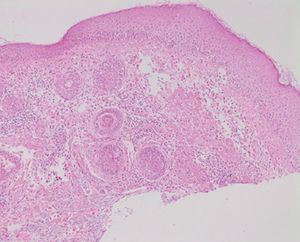

현미경 사진으로 나타난 주사